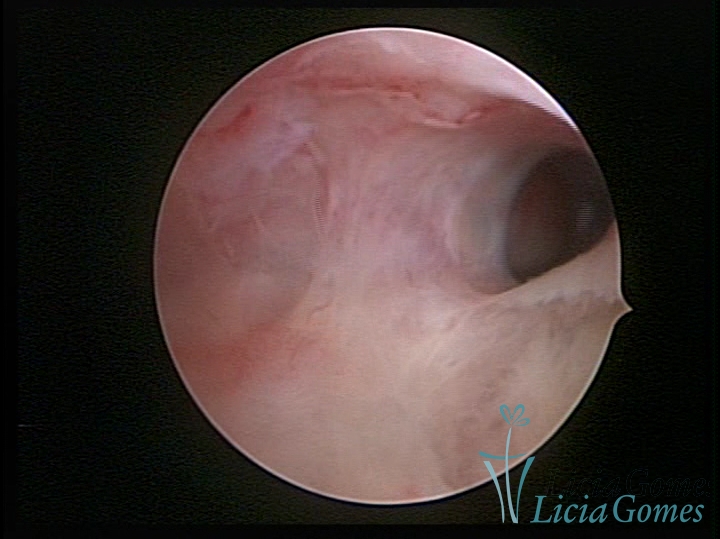

FIBROUS SYNECHIA

Uterine synechiae are scars (adherence) between the surface of the uterine walls, which may occur after the surgical procedure, uterine curettage, or after an inflammatory process in the uterine cavity (endometritis), which may lead to menstrual changes, infertility and obstetric complication such as abortion and premature birth.